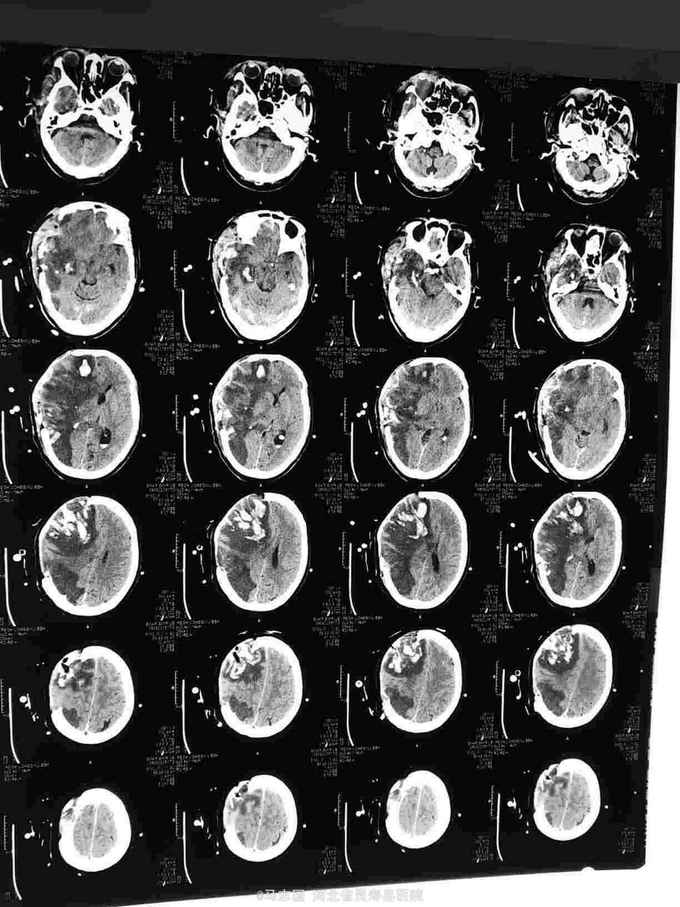

1. 晕厥待查?2. 高血压3级 极高危3.2型糖尿病,给你控制血压,稳定血糖,抗凝抑制血小板聚集,保护脑神经等治疗。入院5个小时后突然意识不清加重,伴恶心呕吐,双侧瞳孔不等大,急查头CT:左侧额顶大面积脑梗塞伴内广泛渗血及脑疝形成。紧急给予颅内血肿清除术,去骨瓣减压术。术后呼吸机辅助呼吸,脱水降颅压等治疗。